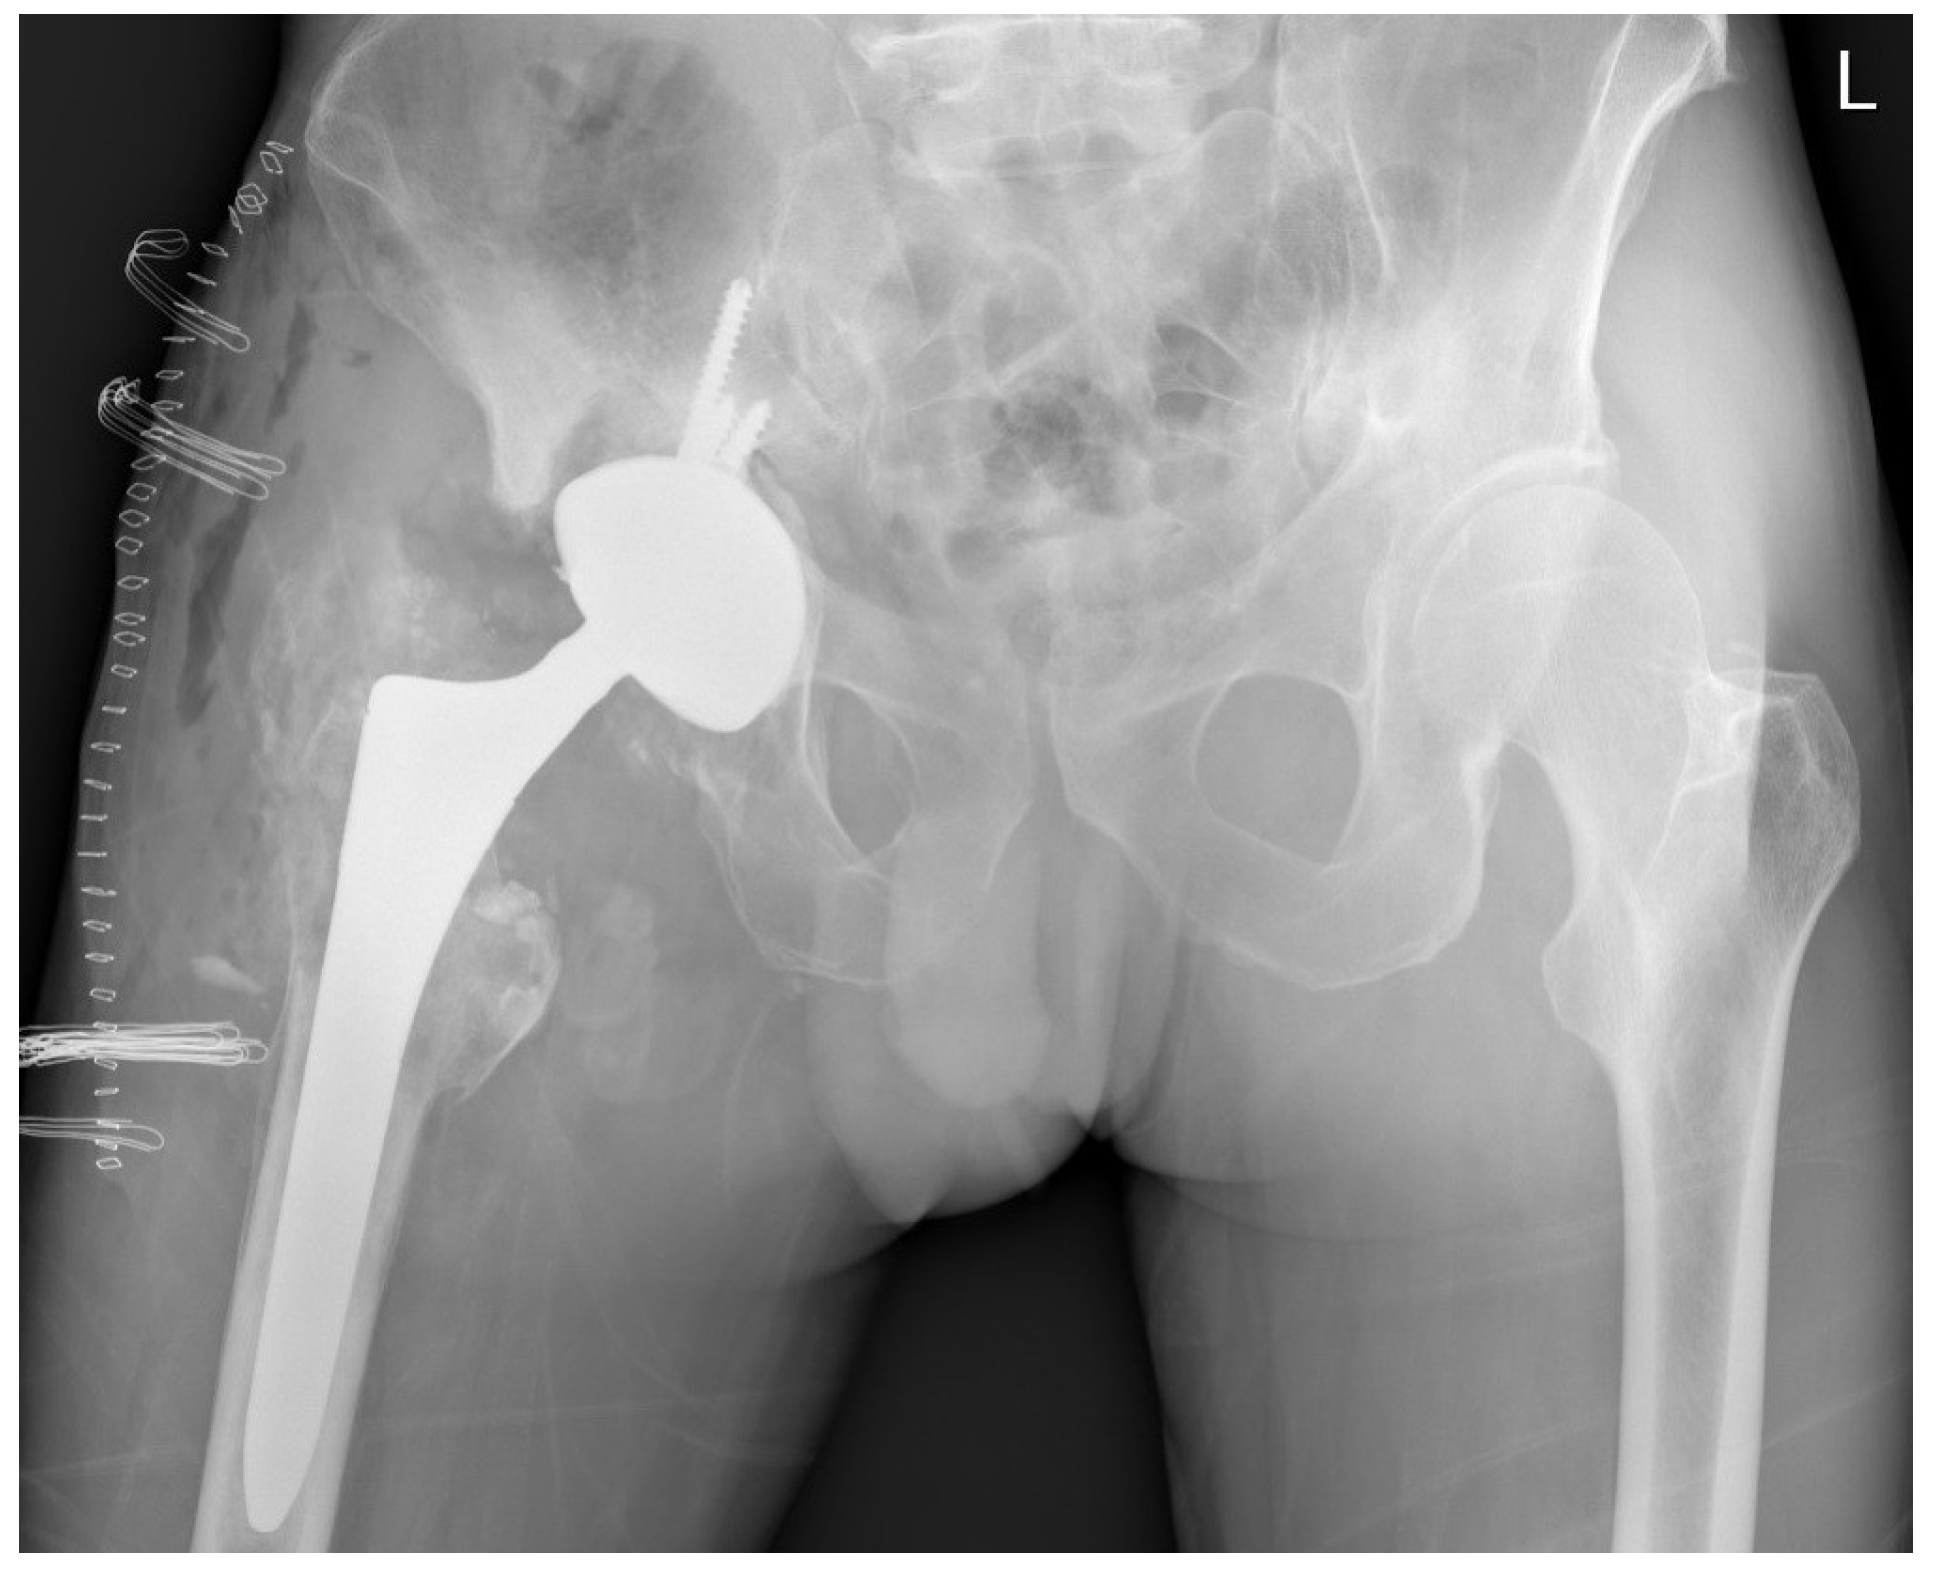

During the revision surgery, the absence of an acetabular liner was noted, and the worn-out ceramic head had directly contacted the acetabular cup, protruding through a central hole formed over time (Figure 3). Pseudo-tumours in soft tissue and severe metallosis near the implant were excised, with tissue samples sent for histological analysis and cultures. Acetabular screws underwent sonication. The stable femoral stem with an intact Morse taper for femoral neck–head coupling necessitated only the exchange of the acetabular component and femoral head. A 58-mm Ti6Al4V press-fit acetabular cup (Delta-TT, Limacorporate, Udine, Italy) with an aluminum oxide matrix composite ceramic liner (Biolox Delta, CeramTec) was inserted and secured with three screws. A 36-mm aluminum oxide matrix composite ceramic revision femoral head with a Ti6Al4V sleeve (Biolox Delta Option, CeramTec) was attached to the original femoral stem, followed by repositioning (Figure 4).

The wound healed uneventfully, and the patient was discharged on the ninth postoperative day. After a 10-day incubation period, all samples were found to be sterile. At the six-month follow-up after the revision THA, the patient reported favorable outcomes. The patient’s HHS was 97 points. Laboratory parameters, including white cell count, hemoglobin level, liver and kidney function, as well as ESR and CRP level, were within normal limits. The radiograph of the patient’s hip depicted stable THA construct without additional osteolysis (Figure 5).

Figure 4. A radiograph of both hips depicting patient’s right hip immediately after revision.